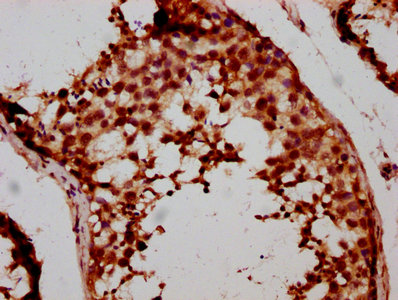

IHC image of CSB-PA861136LA01HU diluted at 1:500 and staining in paraffin-embedded human testis tissue performed on a Leica BondTM system. After dewaxing and hydration, antigen retrieval was mediated by high pressure in a citrate buffer (pH 6.0). Section was blocked with 10% normal goat serum 30min at RT. Then primary antibody (1% BSA) was incubated at 4°C overnight. The primary is detected by a biotinylated secondary antibody and visualized using an HRP conjugated SP system.